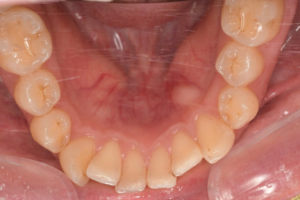

CASE 12

Before

After

基本情報

| 年齢・性別 | 46歳・男性 |

|---|---|

| 主訴 | 歯石をとりたい |

| 治療内容 | スケーリング |

| 治療期間 | 30分 |

| 治療費 | 1,500円(保険診療) |

| リスク・副作用 | 知覚過敏、歯肉退縮、出血 |

| 治療方針 |

歯肉縁上歯石を除去して、次回から歯肉縁下歯石を除去します。 その後も定期的にクリーニングを行い、メインテナンスしていきます。 |